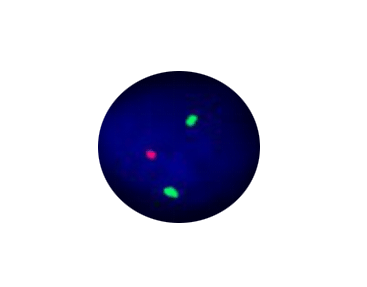

4. This probe can detect 1P deletion and 1Q21 regional amplification.

1q21 Segment Amplification

Probe Description: 1q21/1p36